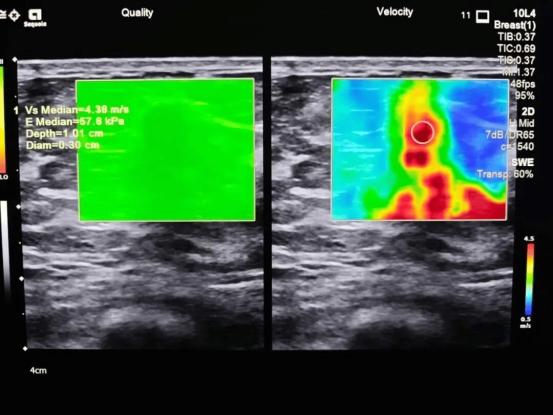

乳腺超声的工作原理与B超检查其他脏器类似,它利用人耳听不见的高频率声波(超声波)穿透乳腺组织。当声波遇到不同的组织界面(如正常的腺体、囊肿的液体或实性肿瘤)时,会产生不同程度的反射。仪器接收这些反射回的声波,并通过计算机处理,在屏幕上形成一幅实时、动态的灰度图像,供医生分析和诊断。它与钼靶最大的区别在于:超声没有放射性辐射,检查过程安全无痛,这对于需要频繁检查的年轻女性和孕期、哺乳期女性来说尤为重要。

优势:洞察致密乳腺的“火眼金睛”超声筛查的核心优势在于其对致密型乳腺的卓越分辨能力。

1.互补钼靶的局限性:亚洲女性中,致密型乳腺的比例非常高。致密乳腺组织在钼靶片子上显示为大片白色,而早期乳腺癌的病灶也恰好是白色。这就好比“在白茫茫的雪地里找一只白兔”,极易漏诊。而超声能清晰地将致密腺体与肿块区分开来,大大提高了检出率。

2.卓越的囊实性分辨能力:超声可以非常准确地判断一个结节是充满液体的囊肿(绝大多数为良性),还是实性肿块。这对于避免不必要的恐慌和穿刺活检至关重要。